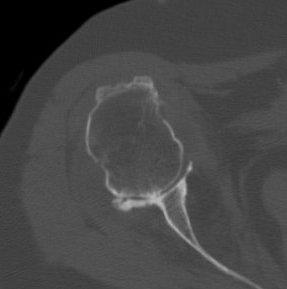

Medial migration with extremely deficient medial bone stock

Glenoid deficiency

Levigne and Franceschi Classification

Three main patterns

| Type 1 | Type 2 | Type 3 |

|---|---|---|

|

Upward migration Superior glenoid wear |

Concentric medial migration Deficient medial bone stock |

Destructive |

Due to rotator cuff insufficiency Most common pattern |